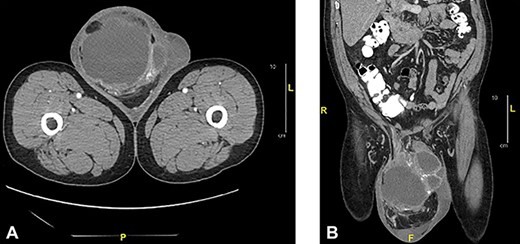

Scrotal ultrasonography revealed a complex septated cystic lesion on the right side of the scrotum (11.2 x 8.9 x 11.6 cm) (Fig. 1). The CT scan showed a large, complex solid and cystic mass (12.0 x 15.55 x 19.0 cm) in the right scrotum; and external to the testicle, a large amount of fat, with no abdominal lymphadenopathies (Fig. 2).

Axial (a) and sagittal (b) CT of abdomen and pelvis with oral and intravenous contrast: showed a large complex cystic and solid mass measuring 12.0 x 15.5 x 19.0 cm in the right scrotum.